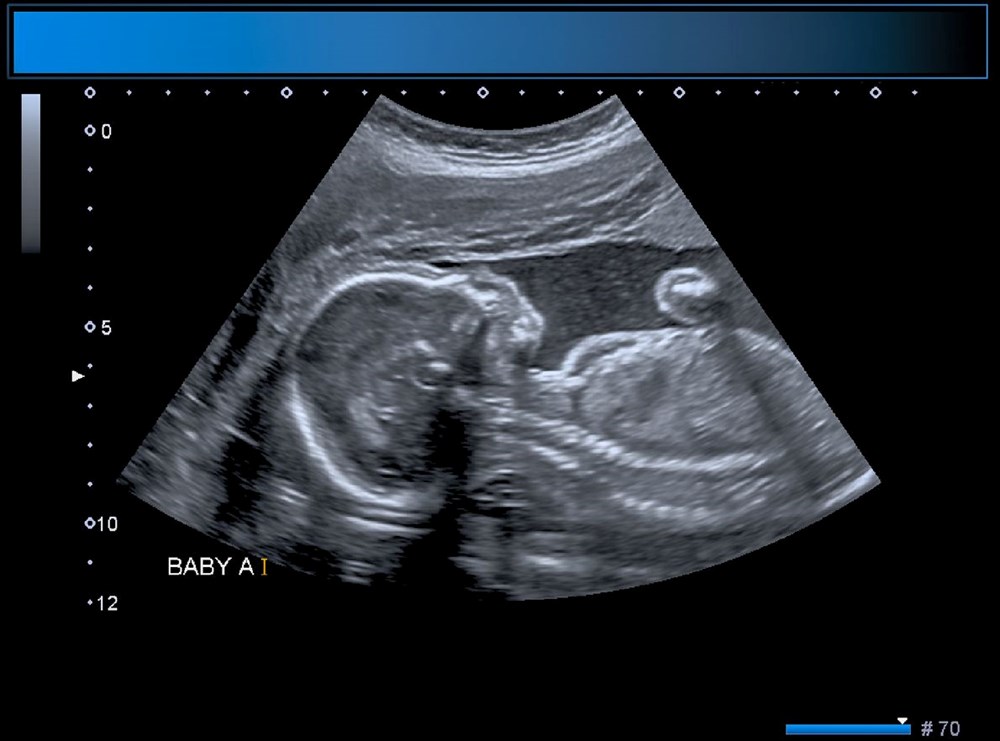

Anneyi 34. haftada ameliyat eden bilim insanları, operasyonu yönlendirmek için ultrason kullandı.

Diğer taraftan, operasyon kapsamında 10 sağlık görevlisinden oluşan bir ekip, annenin karnından uzun bir iğneyi bebeğin beyninin arterlerin etkilendiği kısmına yönlendirmek için ultrason kullandı. Doktorlar, daha sonra damarlara geri akışı engellemek için damar içine küçük bir madde enjekte etti.